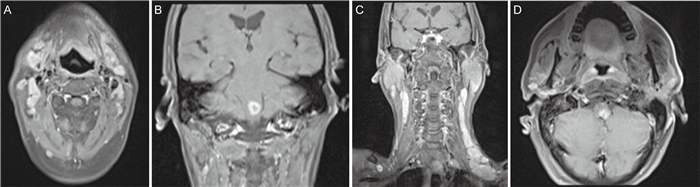

2.5 治疗方案治疗上,建议首选两性霉素B诱导治疗,之后采用伊曲康唑巩固治疗预防复发,无法耐受两性霉素B的患者,可选择伏立康唑[41-42]。推荐两性霉素B(0.5~0.7 mg/kg·d静脉滴注2周)诱导治疗,续以伊曲康唑(200 mg口服q12h)巩固治疗,持续10周后进入二级预防。本例患者经两性霉素B诱导治疗结束,并用伊曲康唑维持治疗,目前皮肤、呼吸系统、消化系统、神经系统等表现均基本消失。患者于近期复查胸腹部CT和头颈部MRI,通过对比发现患者腋窝、纵隔、腹腔淋巴结肿大的症状基本消失,肾上腺未见增粗(见图 6)、颈部肿大淋巴结消失,延髓病变较前缩小(见图 7)。

A, C: Enlarged lymph nodes in the anterior neck disappeared in MRI examination. B, D: Lesion on the left side of medulla oblongata shrank in MRI examination. 图 7 头颅及颈部MRI检查结果(2022年11月) Fig. 7 MRI examination results of the head and neck (November 2022) |